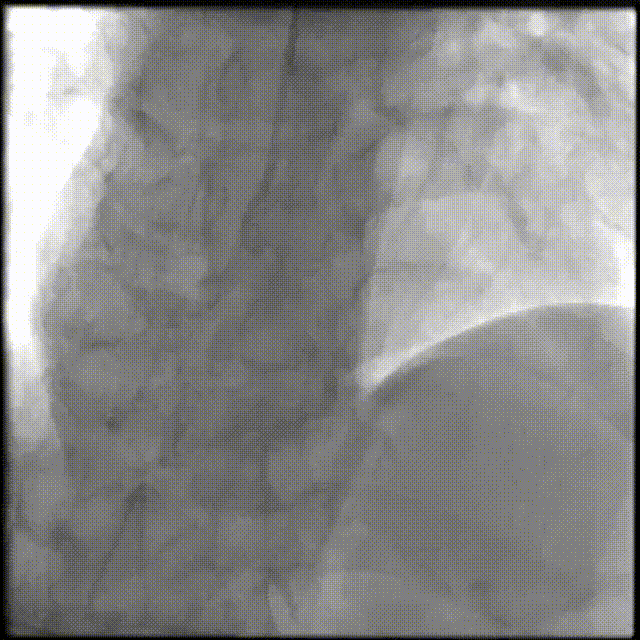

PCI过程-冠状动脉旋切(轨道旋磨)术-1

IVUS导管无法通过,微导管辅助下,将旋磨导丝置于RCA远端,应用1.0mm磨头以13万转反复旋磨钙化病变处(每次15秒,磨头推进速度不超过10 mm/s)

PCI过程-冠状动脉旋切(轨道旋磨)术-2

微导管辅助下,将旋磨导丝置于RCA远端,应用1.0mm磨头以13万转反复旋磨钙化病变处(每次15秒,磨头推进速度不超过10 mm/s)

PCI过程-冠状动脉旋切(轨道旋磨)术-3

共计旋切170秒,术后,狭窄较前减轻